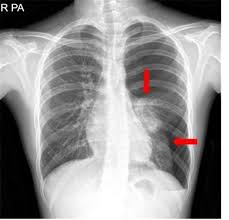

기흉을 가장 손쉽게 진단하는 방법은 흉부 X-선 사진입니다. 위에 언급한 증상을 보이는 환자를 흉부 X-선 사진으로 촬영하면, 대부분 쉽게 기흉을 진단할 수 있습니다. 환자에 대한 진찰 소견으로 진단하는 방법도 있습니다. 병변 부위의 타진상, 공명과도(hyperresonance) 소견, 청진상 호흡음의 감소 소견 등으로 기흉을 의심할 수 있습니다. 흉부 X-선 촬영을 진행하고 전문가가 판독하여 기흉을 확진합니다.

최근에는 흉부 전산화 폐단층촬영(HRCT)등을 시행하여 진단, 치료 방침의 설정에 이용합니다. 그 목적은 선택적인 기흉 환자에게 수술 치료가 필요한지 확인하는 것입니다. 하지만 이 검사는 모든 환자에게 필요하지 않으므로, 전문가와 상의해야 합니다.